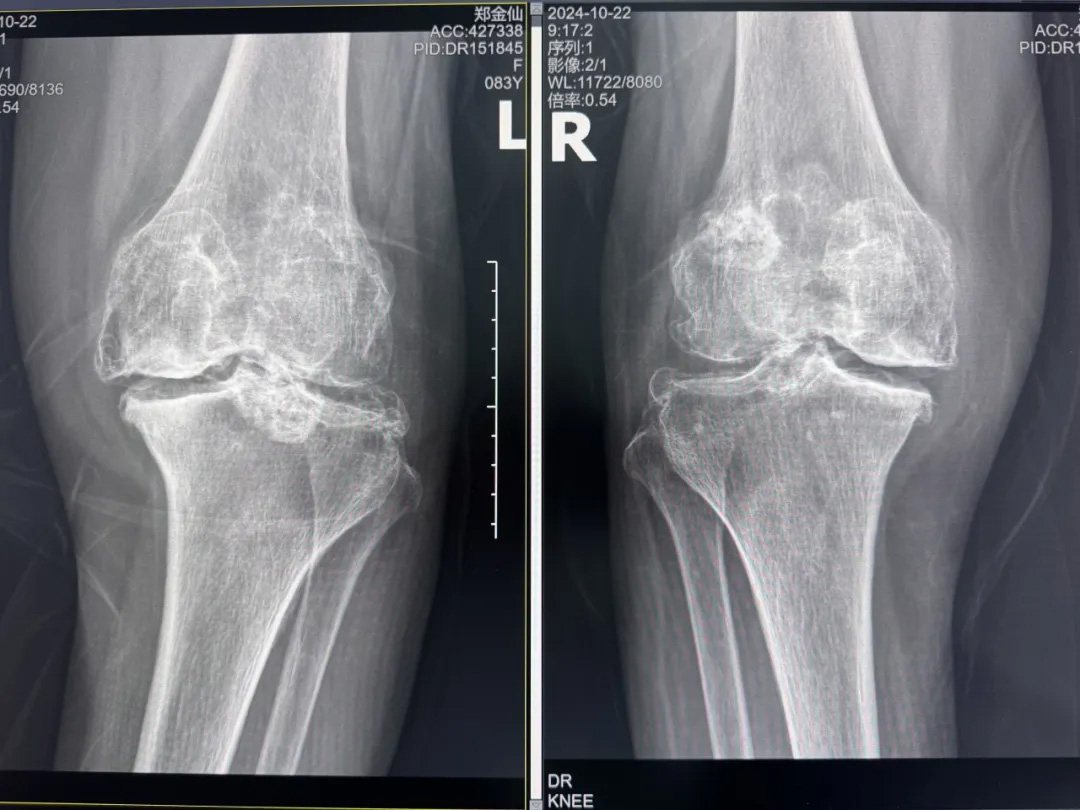

年輕時(shí)愛到處走走的鄭阿婆,晚年卻被雙膝劇痛困在輪椅上長(zhǎng)達(dá)二十年。經(jīng)羅副院長(zhǎng)診斷,她的膝關(guān)節(jié)軟骨幾乎磨光,關(guān)節(jié)嚴(yán)重畸形,呈"羅圈腿",走幾步便疼痛鉆心,連如廁都需家人抱扶。“我這輩子啊,估計(jì)再也站不起來了。”是阿婆最常說的話。

在家人幾乎放棄希望時(shí),AI三維規(guī)劃技術(shù)為這場(chǎng)"關(guān)節(jié)保衛(wèi)戰(zhàn)"帶來轉(zhuǎn)機(jī)。